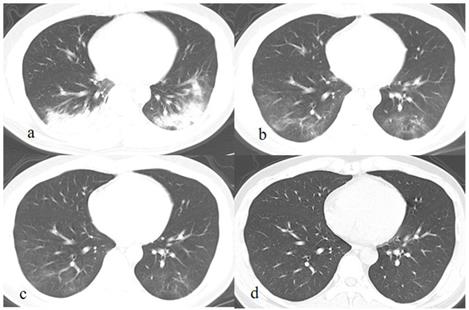

After discharge, all the pulmonary lesions were completely absorbed on the latest CT (Fig. 1-2), the duration of lesions from occurrence to disappearance was 31.6 ± 11.4 days (range: 5-50 days). Among different lesions, duration of GGO was the longest (mean: 29.8 ± 12.1 days, range: 5.0-50.0), which was significantly longer than that of fibrous strips (mean: 23.8 ± 9.5 days, range: 12.0-44.0) (p = 0.046) and consolidation (mean: 9.4 ± 3.6 days, range: 4.0-15.0) (p = 0.000).

Figure 2

A patient exposed to COVID-19 presents with fever, cough, and fatigue for 7 days. The initial chest CT at the first day after admission shows patchy consolidations and GGO in the left and right lower lobes (a). Subsequently (7 and 13 days later), the lesions are continuously absorbed with decrease of extent and density, and fibrous strips are detected in lesions (b, c). On the latest CT scan (36 days later), the lesion is completely absorbed GGO (c).